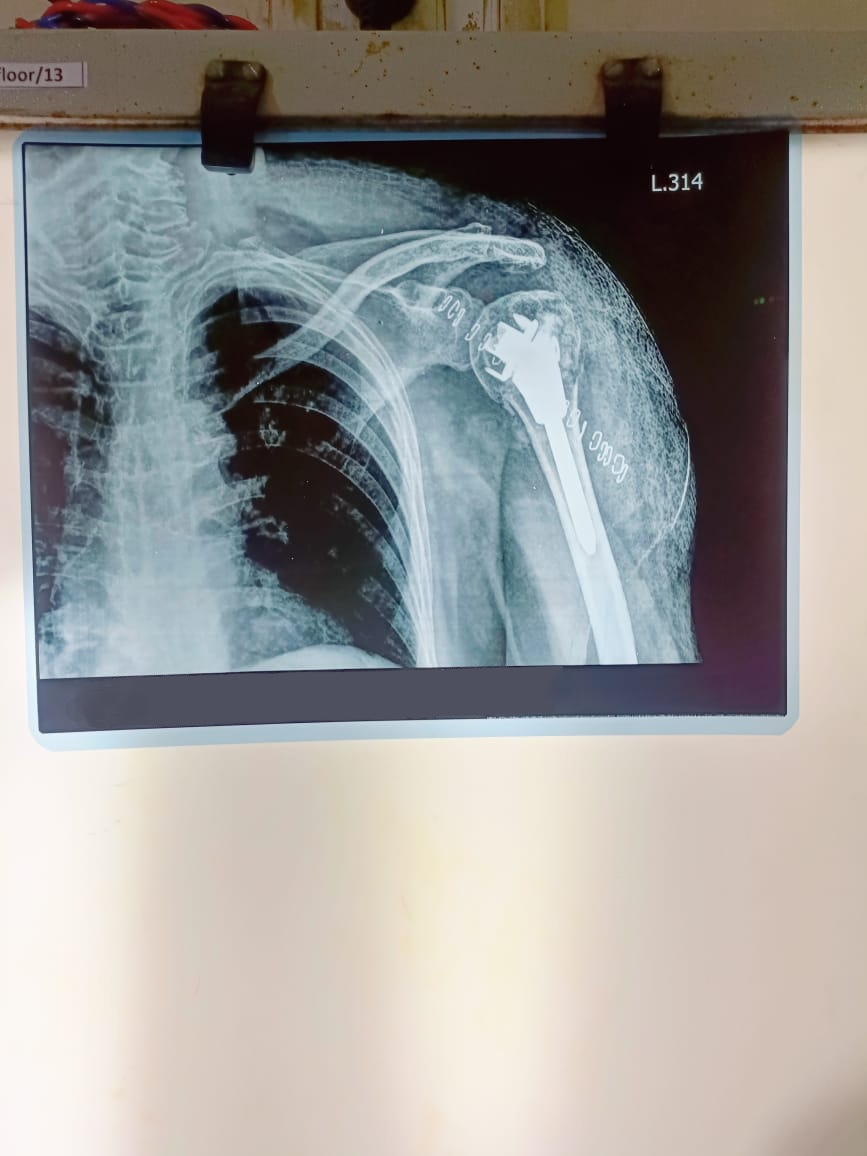

Shoulder Surgery

State new method of fixation of upper end humerus fracture using just unik